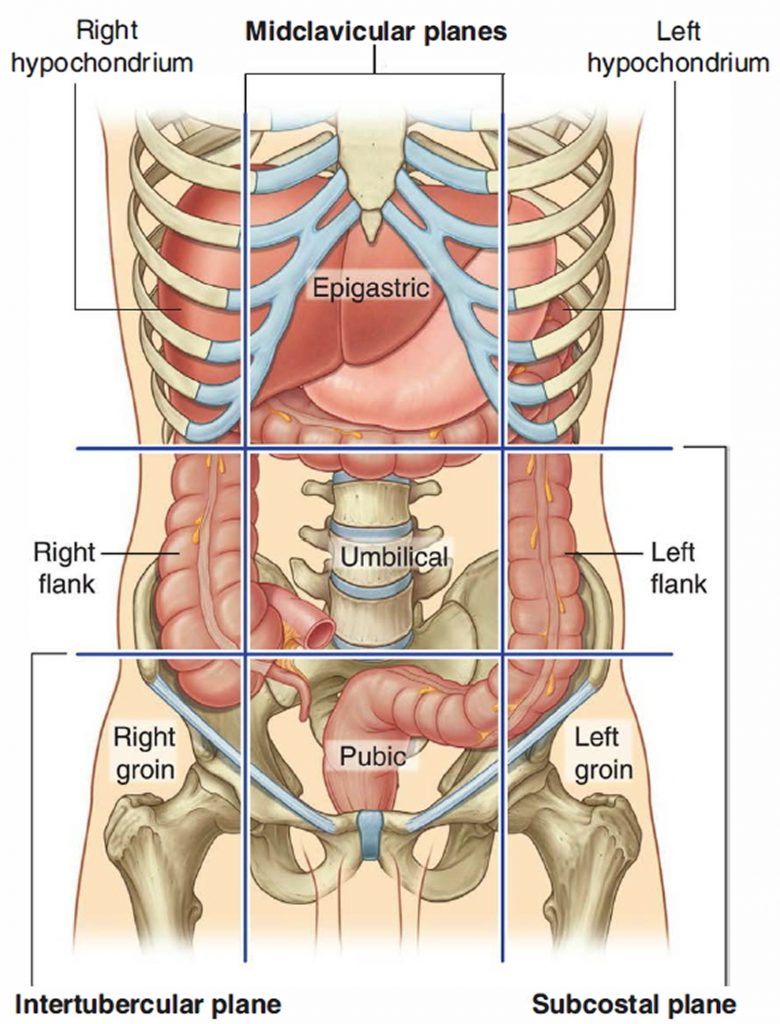

Human Appendix Anatomy, Location and Function of Appendix

Human Appendix Anatomy, Location and Function of Appendix

The appendix is a finger-shaped pouch that sticks out from the colon on the lower right side of the belly, also called the abdomen. Appendicitis causes pain in the lower right abdomen. However, in most people, pain begins around the belly button and then moves. As inflammation worsens, appendicitis pain typically increases and eventually.

The appendix arises from the posteromedial surface of the cecum, approximately 2-3 cm inferior to the ileocecal valve, where the three longitudinal bands of the taeniae coli converge. It is a blind diverticulum which is highly variable in length, ranging between 2 and 20 cm. The appendiceal mesentery is called the mesoappendix 1,2.

Appendix Location, Function, Anatomy and FAQs

The appendix is a narrow blind-ended tube that is attached to the posteromedial end of the cecum (large intestine). It contains a large amount of lymphoid tissue but is not thought to have any vital functions in the human body.. In this article, we shall look at the anatomy of the appendix - its anatomical structure and relations, neurovascular supply and lymphatic drainage.